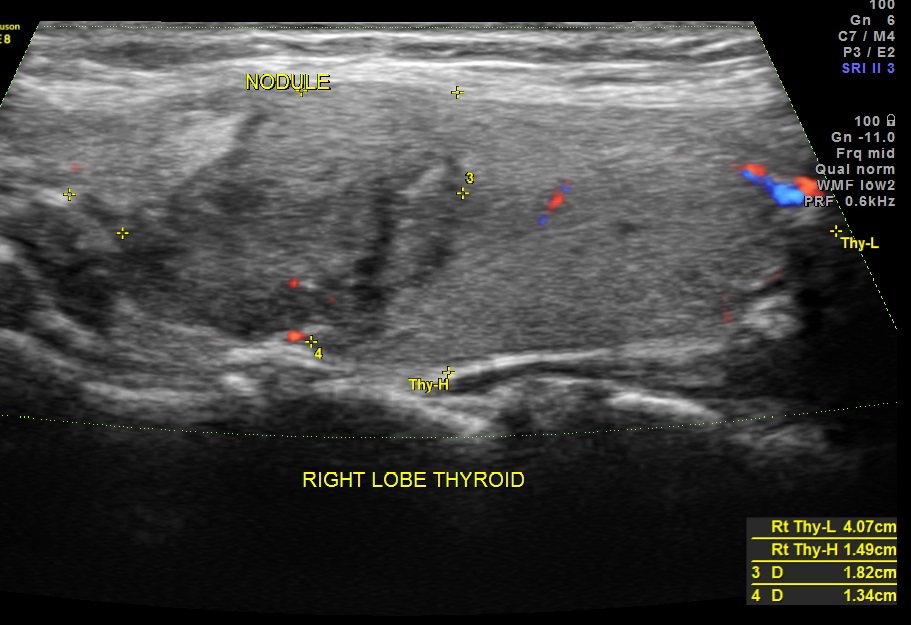

This was a 40 year old lady evaluated for a palpable neck mass on the right side.

Ultrasound revealed he following .

The right lobe of the thyroid revealed an irregular mass , with indistinct margins , punctate calcification and vascularity within and around the nodule.

The features of a thyroid mass with irregular margins, punctate calcification and vascularity within and surrounding the mass is suggestive of PAPILLARY CARCINOMA OF THE THYROID.

FNAC was done and confirmed the diagnosis of PAPILLARY CARCINOMA OF THE THYROID.